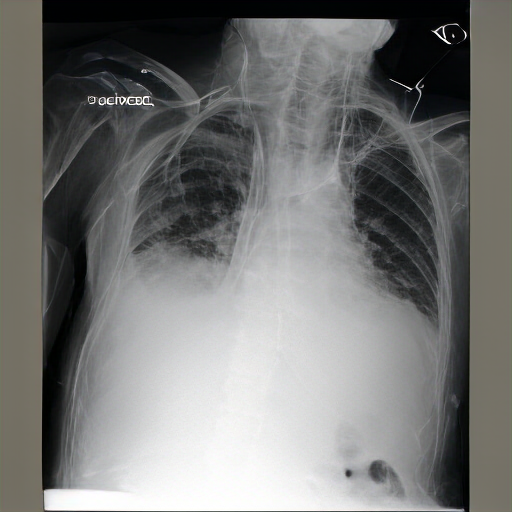

Right central venous catheter terminates in the right atrium. No pneumothorax. Overall low lung volumes are stable. Diffuse right paratracheal and pulmonary mass is better assessed on recent prior chest imaging. No underlying consolidation is identified. Retrocardiac opacity represents atelectasis and may also be secondary to patient rotation and low lung volumes. No pleural effusion or pneumothorax. Left-sided lateral airspace opacities persist which may relate to the known effusions. Mediastinal contours are unremarkable.

The lungs are hyperinflated, consistent with COPD. No consolidation or pneumothorax. Linear opacities are seen in the right lower lung, likely due to atelectasis. Streaky opacity within the right lung base is again seen without correlate on the frontal view, possibly representing atelectasis or overlying structures of the right lower lobe. No pneumothorax or pleural effusion is detected. The cardiac silhouette is not enlarged, and mediastinal contours appear within normal limits.

The image is a radiograph of the chest, showing the thoracic cavity structures. Multibibasilar opacities could represent overlap of the apex. No clinical evidence for pneumonia. There are new bilateral infrahilar infiltrates and mild pulmonary edema with flattening of the diaphragmatic contour.